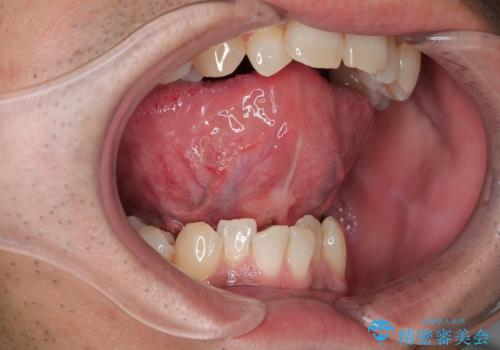

【舌小帯切除】ら行が言いづらい

- 滑舌が気になり来院されました。

舌小帯を形成することにより、滑舌の改善を図ります。

舌小帯形成では舌の可動域拡大や滑舌の改善を行うことが出来ます。

また、当日に処置が可能です。